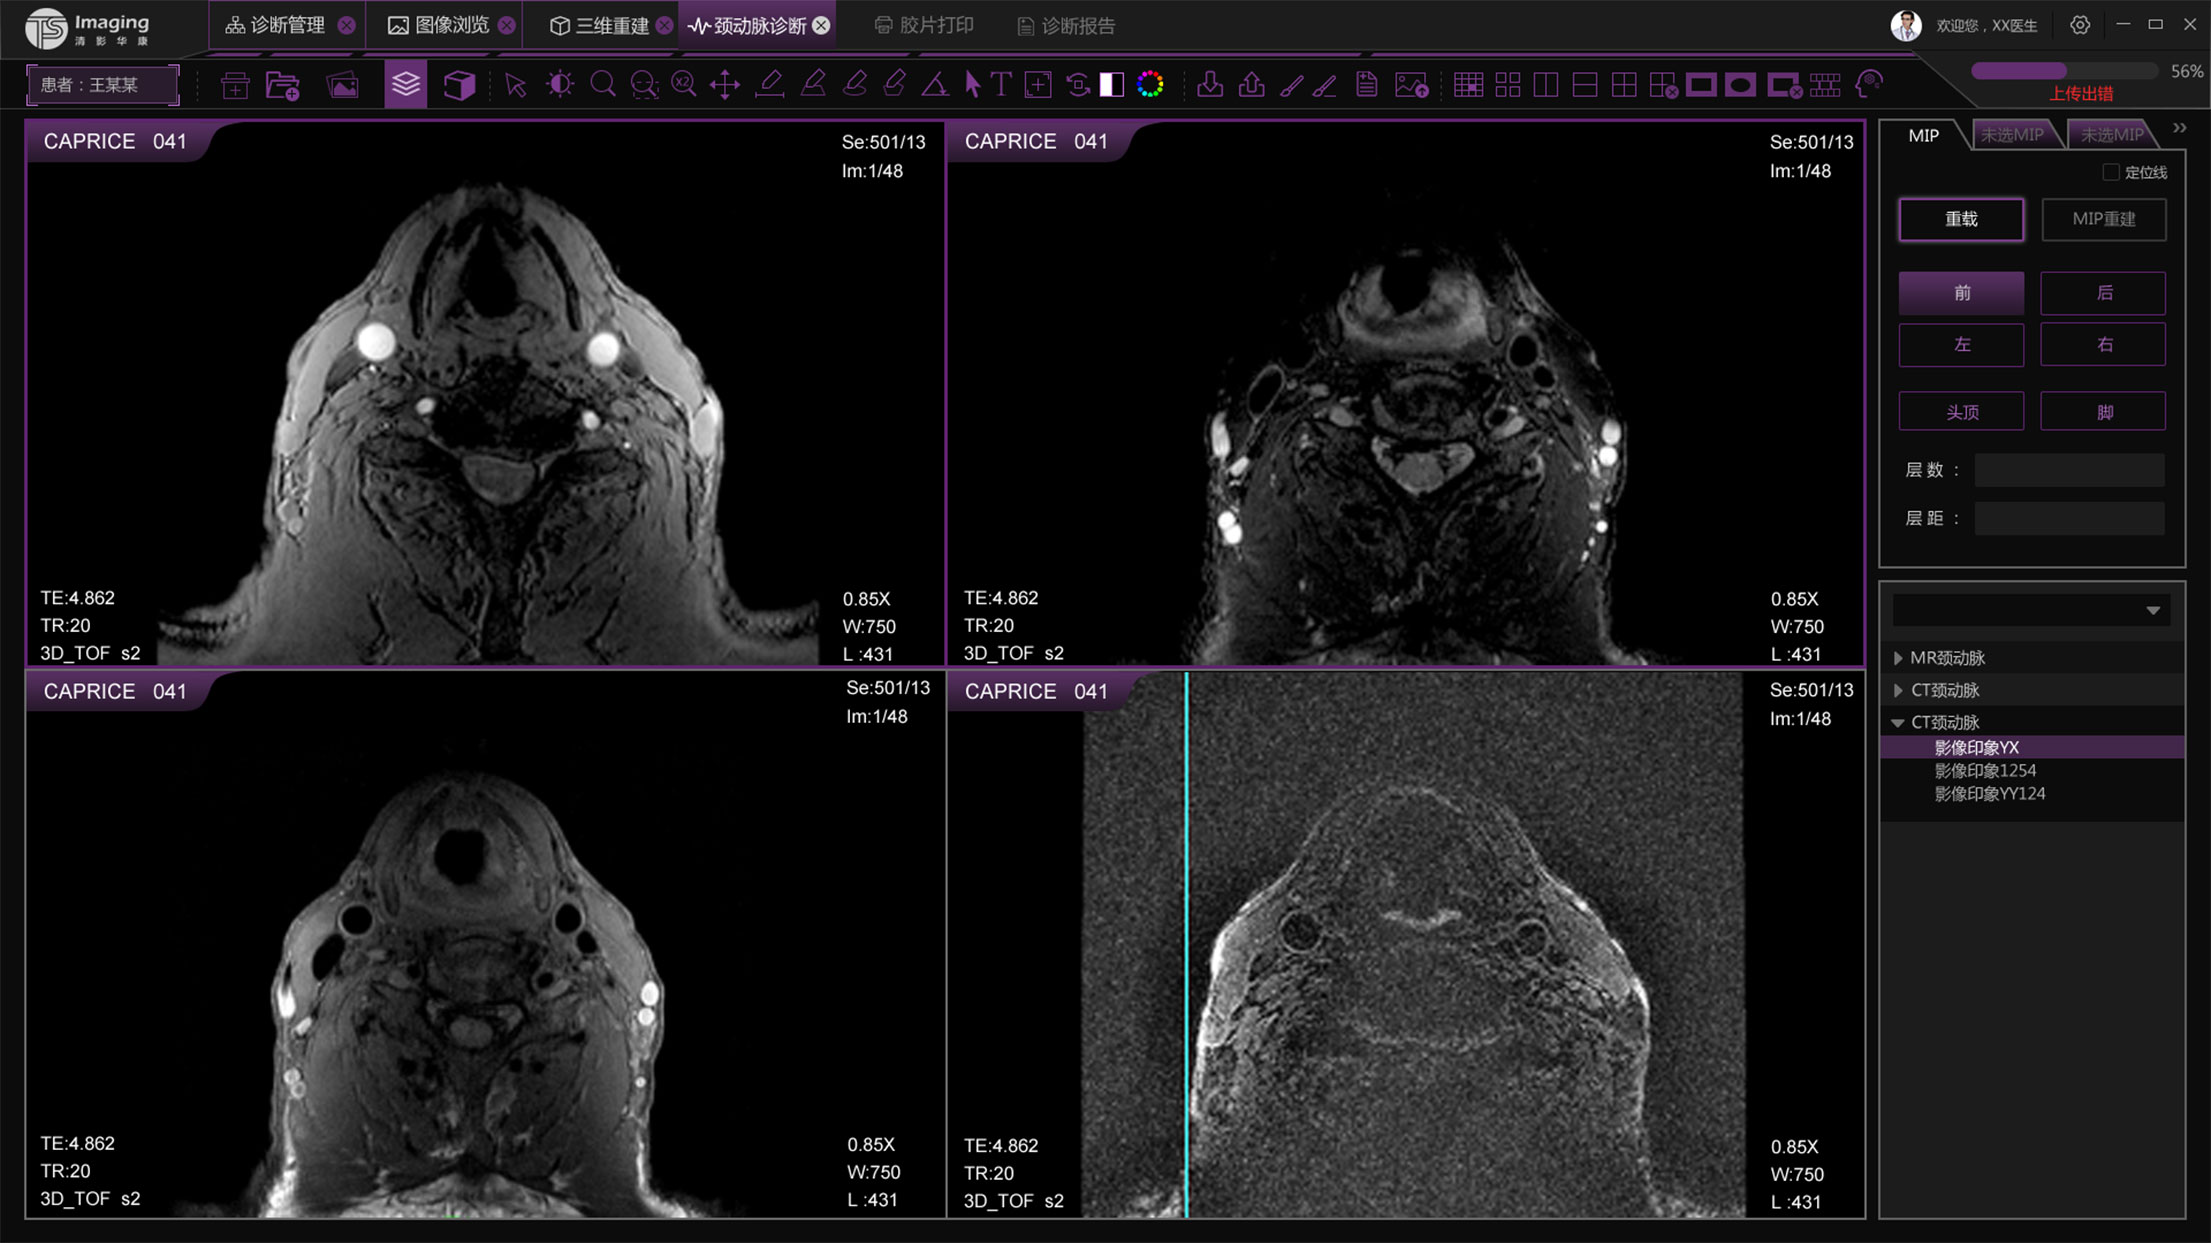

頸動脈診斷頁面

頸動脈診斷頁面整體布局和三維重建比較相似,最大的區別是右側的操作區域,血管分析都為按鍵操作,通過間隔的大小分成三部分。單層切片除了按鍵還有下拉菜單的操作。

頸動脈診斷原型